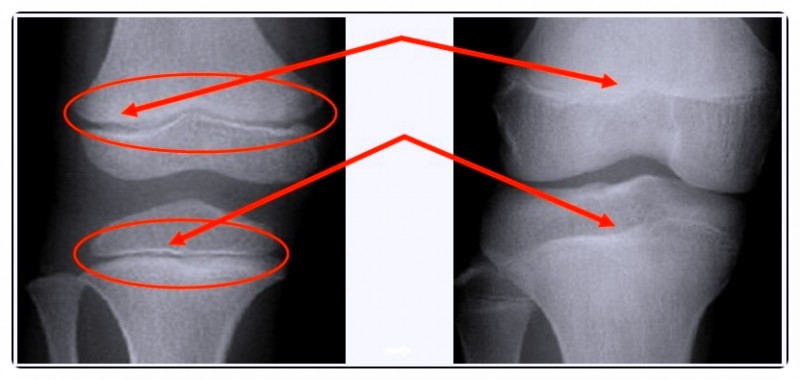

성장은 단순히 뼈가 길어지는 과정이 아닙니다.

뼈와 근육, 인대의 균형이 함께 맞아야 건강한 성장이 이뤄지죠.

하지만 잘못된 자세나 걸음걸이로 인해 성장판에 지속적인 압력이 가해지면, 성장 속도가 늦어질 수 있습니다.

자세 교정은 단순히 외형을 바로잡는 것이 아니라, 성장판의 기능을 보호하고 몸의 중심을 바로 세우는 과정입니다.